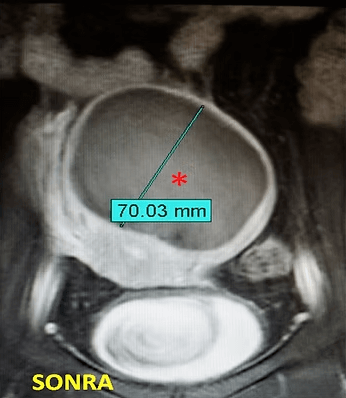

32 yaşında, kansızlık, gaz, sık idrara çıkma şikayetleri var. Emar’da 9 cm çaplı tek miyom (*) mevcut. Tek seans perkütan ablasyon sonrası miyomun belirgin küçüldüğü izleniyor. İşlemden 5 ay sonra hasta şikayetleri kalmamıştır.